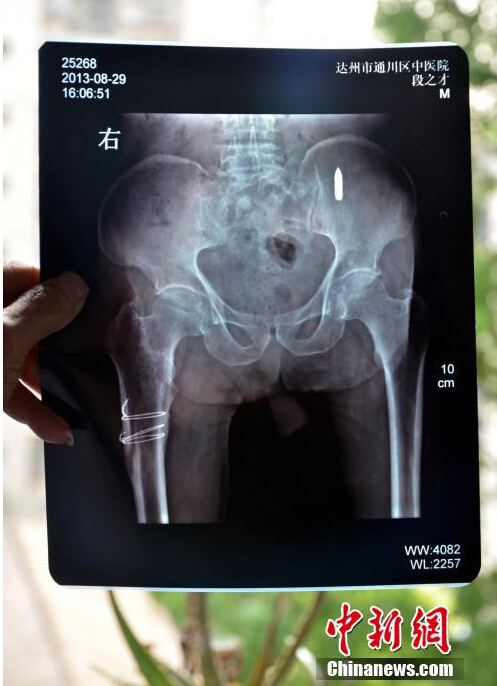

11 июня, ?Жэньминь жибао? онлайн -- Пожилой ветеран войны сопротивления японским захватчикам из города Дачжоу провинции Сычуань показывает рентгеновский снимок, где видна пуля в правой подвздошной кости.

Согласно результатам медицинского обследования, размер пули составляет 3 см. Поскольку пуля - это металлический предмет, поэтому может долго находиться в костях. Как предполагают медики, пуля попала в тело человека, когда он был ранен в лежачем положении через ягодицы.